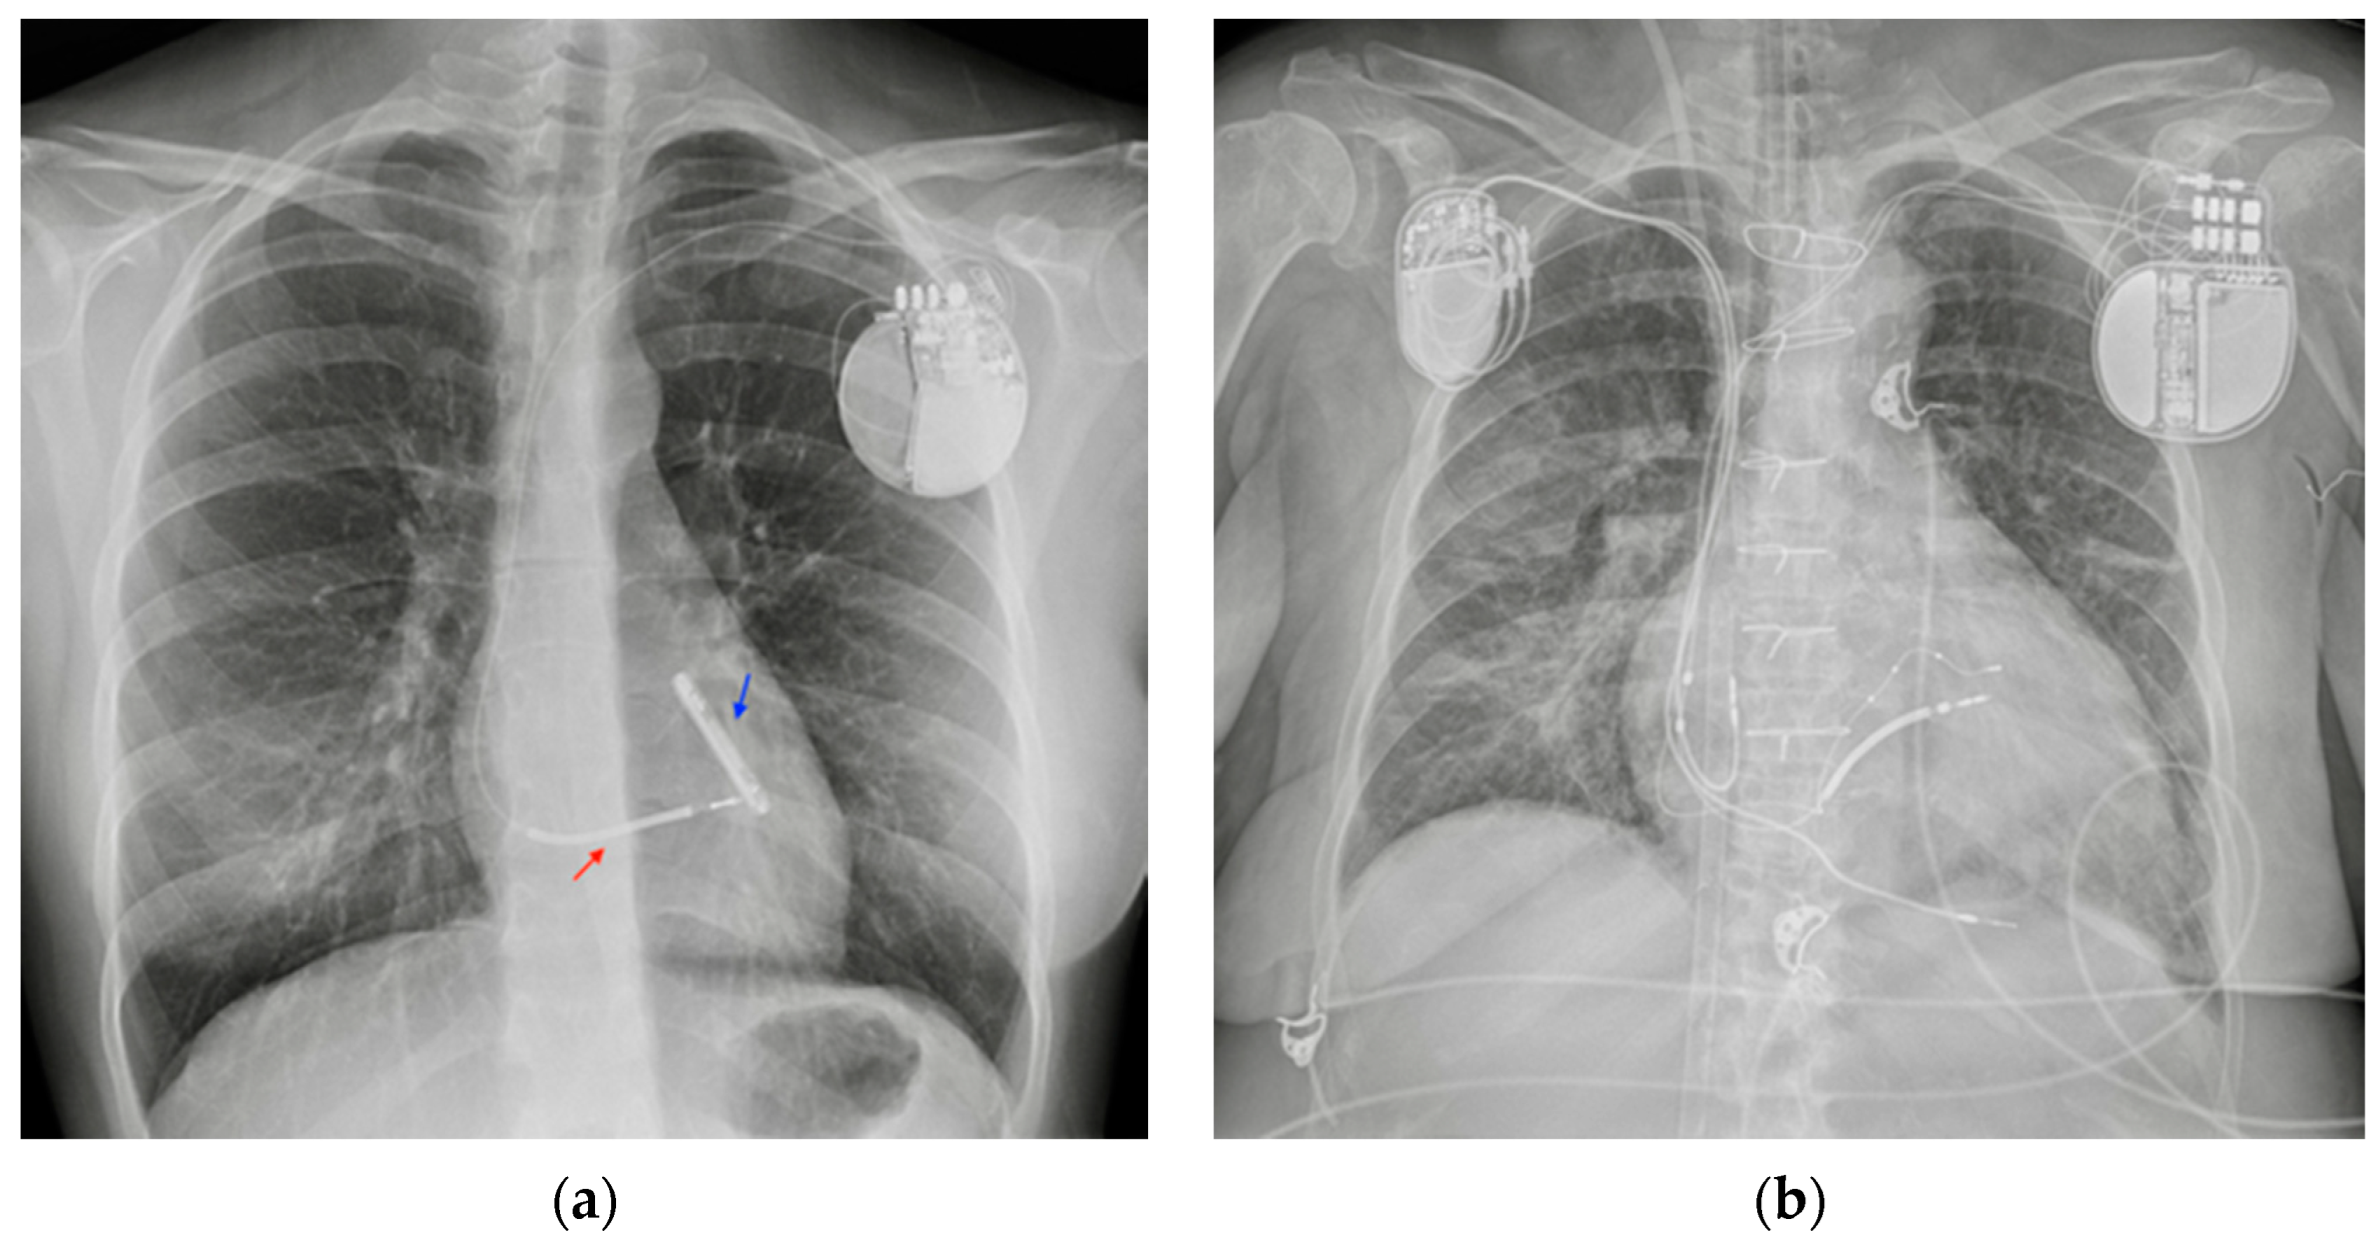

AICD and PM can be distinguished on a CXR by the presence of ICD shock coils: a thick metal segment placed in the end of the lead. Combined ICD-PM devices also exist, known as “cardiac resynchronization therapy” (Figure 14).

Figure 14.

PM and AICD. (a) A normally inserted AICD. The thick coil can easily be seen at the end of the lead (red arrow). This patient also has an implantable loop recorder (blue arrow). (b) A patient with both a PM (right side) and an ICD–biventricular pacemaker combination (left side); also in the image, a right jugular CVC, an ETT and an extracorporeal membrane oxygenation (ECMO) cannula whose tip reaches the right atrium via the IVC (femoral access) (Table 4).

CXR is useful after the positioning of these devices to check for the correct location of the electrical leads and to check for their integrity on follow-up examinations. Twiddler’s Syndrome, the consequence of the patient manipulating the device in its pouch, can result in misplacement of the wires that are visible on the CXR as twisted around the PM body [22].